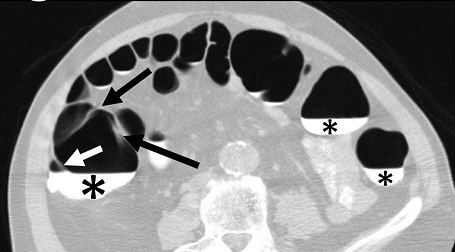

A single reviewer evaluated all data sets using a DICOM image viewer (OsiriX v4.0) for inclusion into this study. Inclusion criteria were: (1) adequate colonic distension and (2) presence of measurable folds. Having a minimum of at least five consecutive measurable haustral fold pairs in a given colonic segment was established as a marker of adequate bowel distention for optimal measurement of folds. Measurable folds were defined as folds that were not obscured or distorted by retained fluid, luminal collapse, tortuosity or diverticulosis. As haustral folds meet at the teniae coli, two of the three folds were each measured with the most dependent fold excluded; the most dependent folds were most often obscured by fluid if present (Figure 1A). Measurements of fold heights were made on 2D multiplanar reformations; the imaging plane demonstrating the folds in cross-section was established for optimal measurement of fold heights (Figure 1B). Due to the high frequency of tortuosity, suboptimal distention relative to other colonic segments, distortion of the folds and diverticulosis relative to other colonic segments, the sigmoid colon was not included in this study.

Figure 1A.Axial CT-Colonography image demonstrating dependent fluid tagging (*) obscuring a dependent haustral fold (white arrow) with a pair of unobscured, non-dependent haustral folds (black arrows). Note: difficulty in visualization of haustral fold pair due to slice selection in the axial plane.